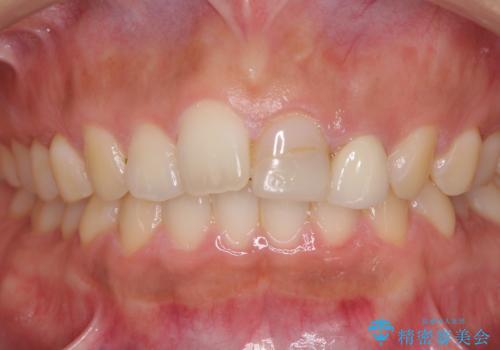

- 中学生の時にスポーツで折ってしまった前歯が変色してしまったとのことで来院された患者様です。

結婚式に向けてオールセラミッククラウンにて仕上げていくこととしました。

既にクラウンが装着されていた歯は歯根の先端に病変が認められたため、根管治療を行うこととしました。

仮歯装着の時点で自然な見た目となり、オールセラミッククラウンを装着した際には、まるで自分の歯のようと喜んでくださいました。